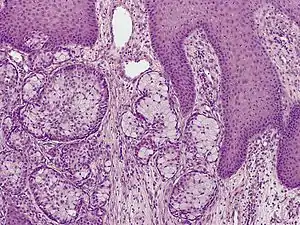

| Eccrine carcinoma, alveolar type | |